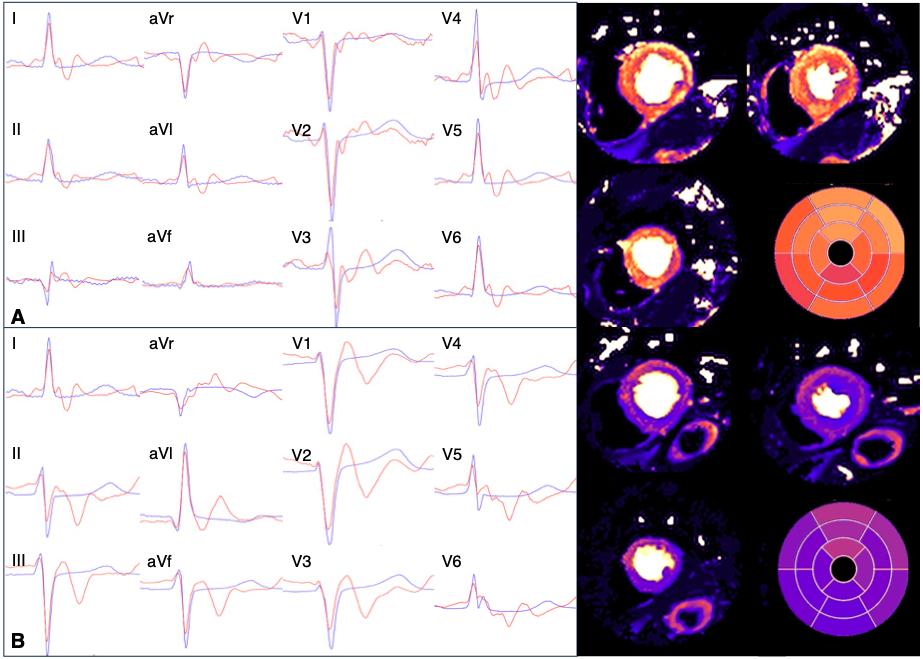

In-bore and reference ECGs (Figure 2) were strongly correlated (r=0.81, interquartile range 0.720.88), and mean differences in QRS and QT durations were small (12.5ms [95% limits of agreement -42.5, 17.5ms], and -5.5ms [-54.6, 43.6ms] respectively).

Ischemic ECG changes (Figure 3) during adenosine predicted inducible ischemia (stress myocardial blood flow <1.75ml/g/min) with sensitivity 91.7% (95% confidence interval (61.5, 99.8), specificity 59.3% (45.0, 72.4), positive predictive value 33.3% (18.0, 51.8), negative predictive value 97.0% (84.0, 99.9) and area under curve 0.74 (0.61, 0.86).